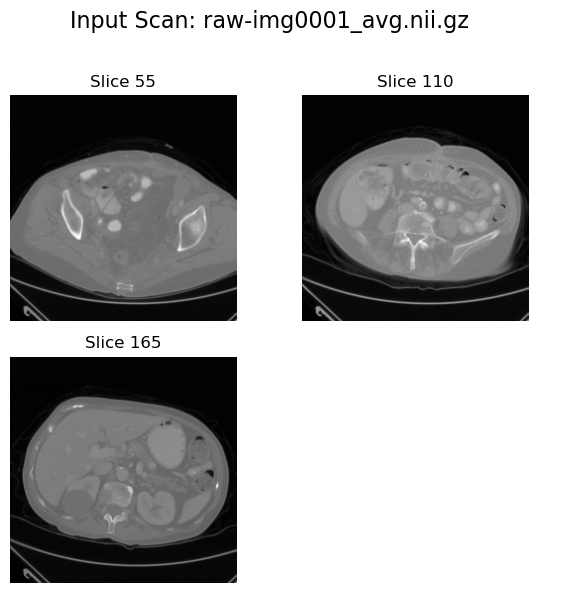

Input view#

plot_input_scan(input_path=image_path, num_slices_to_plot=3)

2025-08-04 10:51:49,784 - INFO - Input data shape: torch.Size([229, 229, 220])

../../../_images/38cc35eba586163eb8f685409a5f5a69e7048739abe2a51af1b28d83e27e23a9.png